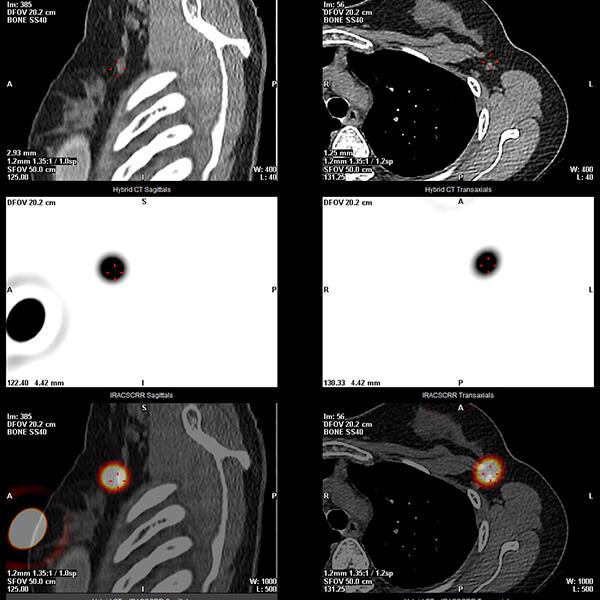

Après une attente d’une heure à deux heures, une série d’images sera ensuite réalisée en position allongée afin de visualiser le ganglion sentinelle.